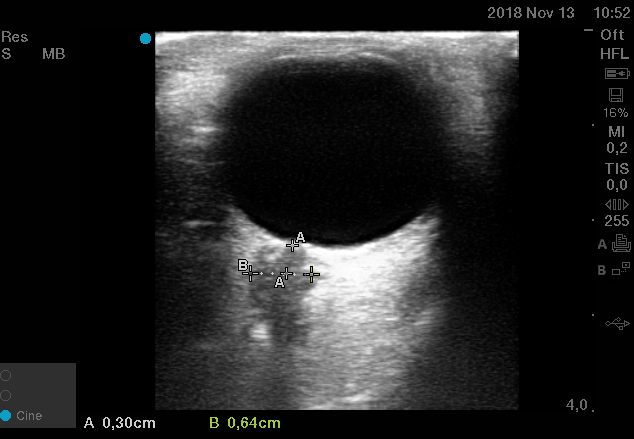

Curso de ecografía crítica en todas sus modalidades (ecocardiografía transtorácica y transesofágica, ecografía pulmonar, vascular, cerebral, FAST) dirigido a: médicos intensivistas, emergenciólogos, anestesiólogos, internistas, médicos de familia, neumólogos, cardiólogos y a todo aquel interesado por utilizar la ecografía como parte del examen físico del paciente crítico.

En nuestro afán por seguir el trabajo empezado hace ya varios años desde Europa (España) por impulsar la ecografía crítica para intensivistas, emergenciólogos, anestesistas, internistas, subespecialistas de obstetricia crítica, neumólogos y todo aquel médico interesado en aprender a utilizar la ecografía como parte de su examen físico, ahora desde Centroamérica (Panamá), hemos escrito el primer libro Latinoamericano-Europeo de ecografía crítica sub-especializado y dedicado exclusivamente al paciente con shock de cualquier etiología (obstructivo, distributivo, cardiogénico, hipovolémico) que involucra todas las modalidades ecográficas: ecocardiografía, ecografía pulmonar, vascular, abdominal, del sistema nervioso central/doppler transcraneal, etc) en el que participan muchos expertos en sus respectivas áreas tanto de Europa como de América y también algunos profesores del EDEC (Diploma Europeo de ecocardiografía / ESCIM- Sociedad Europea de Medicina intensiva).